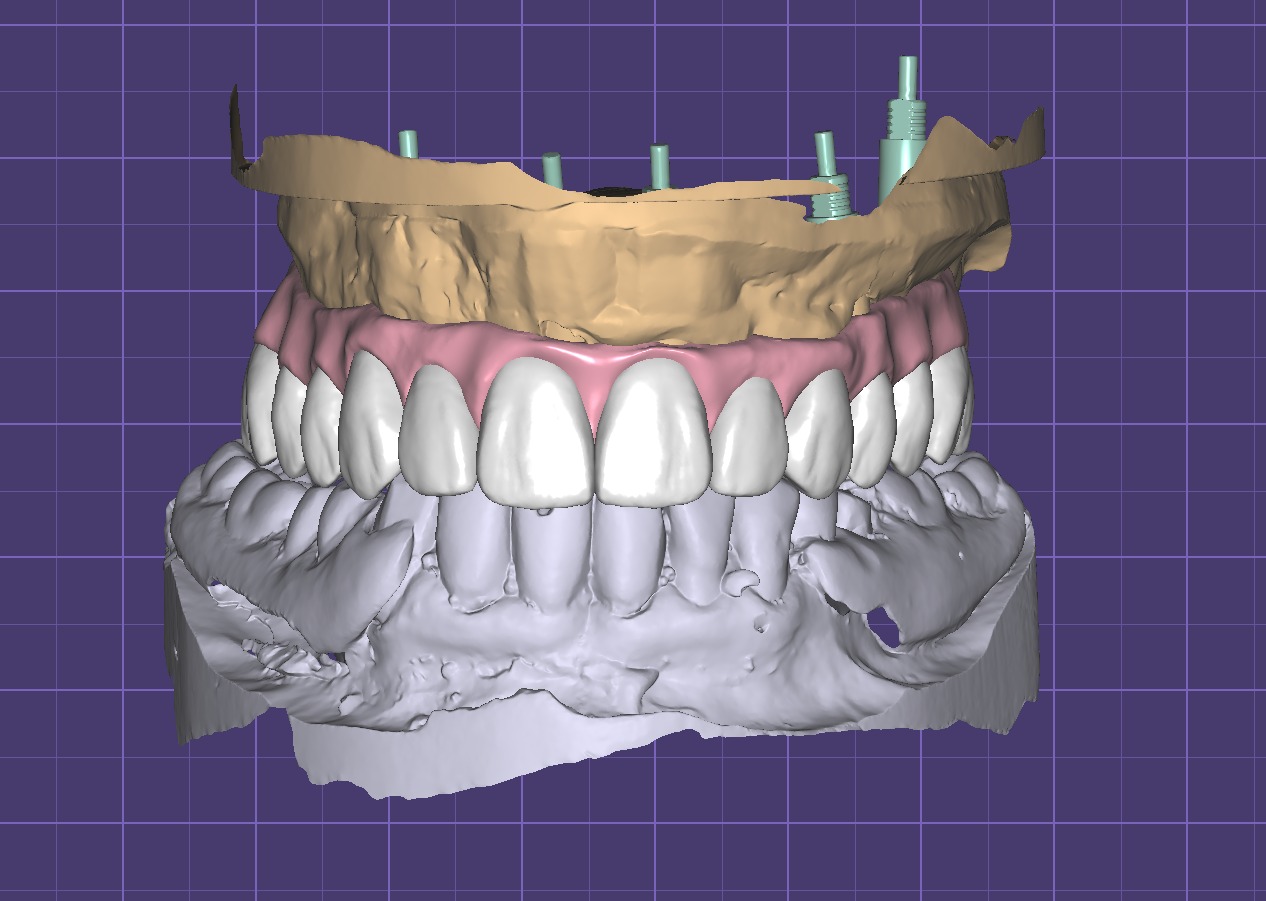

Dr. Ricardo Velázquez García es un dentista destacado en Colima, especializado en implantes dentales y cuidado integral de la salud bucal. Ubicado en el Centro Médico Puerta de Hierro, en Calle Ignacio Sandoval 1699-Consultorio 312, Girasoles, ofrece un ambiente profesional y acogedor para todos sus pacientes. Con una sólida reputación respaldada por una calificación de 5 estrellas basada en 235 opiniones, el Dr. Velázquez se distingue por su atención personalizada y la calidad de sus tratamientos. Sus pacientes valoran especialmente la amabilidad del equipo, la limpieza profunda y los resultados efectivos, como blanqueamientos dentales y procedimientos de bonding. La clínica cuenta con tecnología avanzada y un equipo comprometido en brindar una experiencia cómoda y segura. Para agendar una cita o solicitar información, puede comunicarse al teléfono 312 688 2357 o visitar su sitio web oficial https://dentaldesign.acecli.cloud/. El Dr. Ricardo Velázquez García es una opción confiable para quienes buscan mejorar su sonrisa y mantener una salud dental óptima en Colima.

Dr. Ricardo Velazquez García is a highly regarded dentist in Colima, specializing in dental implants and comprehensive oral health care. Located at Centro Medico Puerta de Hierro, Calle Ignacio Sandoval 1699-Consultorio 312, Girasoles, the clinic provides a professional and welcoming environment for all patients. With a 5-star Google rating from 235 reviews, Dr. Velazquez is known for his personalized approach and high-quality dental treatments. Patients appreciate the friendly and professional staff, thorough cleanings, and effective results including teeth whitening and bonding procedures. The clinic is equipped with advanced technology and a team dedicated to delivering a comfortable and safe experience. To schedule an appointment or request more information, contact the office at 312 688 2357 or visit the official website at https://dentaldesign.acecli.cloud/. Dr. Ricardo Velazquez García is a trusted choice for those seeking to improve their smile and maintain excellent dental health in Colima.